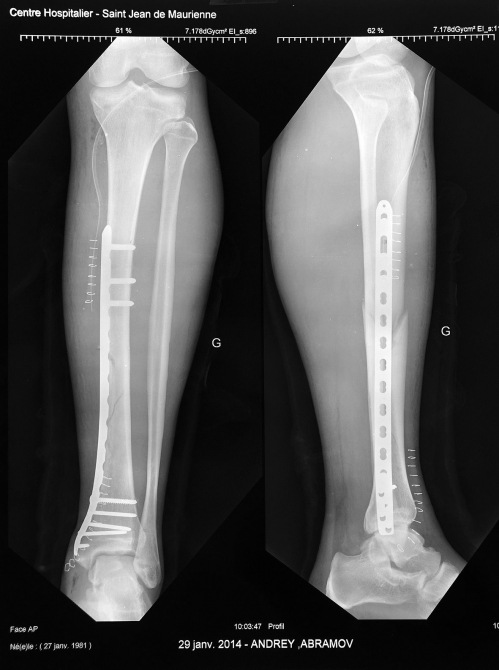

Ну, и немного про страховку. Угораздило меня попасть лыжей под дерево на краю трассы – удар, рывок, лыжа отстегнулась, но было поздно…голень оказалась слабее. Спасатели прибыли оперативно и довезли до подъемника – там было метров 300 всего. Через часик прибыла скорая из St. Jean de Maurienne, ближайший госпиталь там. Страховая сказала, что все оплатит (полис от Ренессанс), чему поверили и спасатели, и врачи. Быстро стало понятно, что просто гипсом мне не отделаться – назначили операцию на следующий день.

Госпиталь пристойный, титан швейцарский, кормят французской кухней, есть хирург, обучавшийся в Киеве и говорящий по-русски. Итого шесть дней. Прямо от госпиталя начинается сеть тропинок для костылинга, есть парапланерные старты, в городке бесплатный вай-фай. Но вот лыжи оставили в гараже, и какая-то французская сволочь их оттуда подрезала. Так что если стафф новый и красивый, лучше настоять, чтобы его принесли в палату – надежнее будет. А комплект был отличным - всего 3750 г. лыжи с креплениями, правда, в следующем сезоне будет и карбоновая версия Конвертов, выигрыш в весе 380 г., как раз компенсирует разницу в весе Динафитов и Фритчей.

Надеюсь что и пластина сделает свое титановое дело, и сезон будет катальным:)